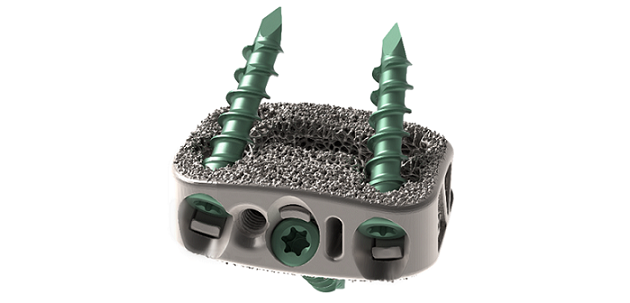

Supporting the full implant treatment process, Streamlining Additive Manufacturing For Spinal Implants,

Streamlining Additive Manufacturing For Spinal Implants, NexGen® Complete Knee Solution,

NexGen® Complete Knee Solution, Zero-P Natural Anterior Cervical Plate,

Improving off original VITA 46 standards, Amphenol's R-VPX, Evolution Spine New Product Launch – Ortho Spine News,